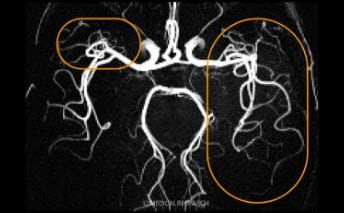

テスラの違い

【要確認】メディカルリサーチでは、3.0T(テスラ)の機器を用いてMRI撮影を行っています。

3.0T(テスラ)の機器で撮影すると末梢脳血管まではっきりと確認することができます。-

1.5T(テスラ)診断画像 -

3.0T(テスラ)診断画像